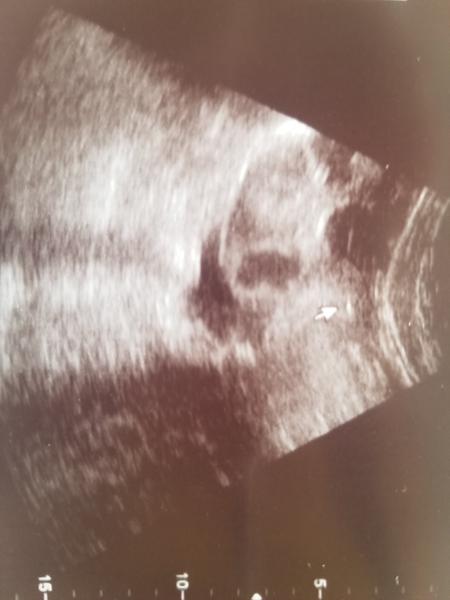

@zuzik5891 ten vklad bol oki uplne, prides ako na gyn. prehliadku a je to tak ako ked ti robia ster z krcku s tym ze ti robia sono zhora zaroven, trva to asi minutku ak vobec a vobec to neboli 🙂 potom som polezala dali mi obraztek a finito :D to ta bodka to je ono hehe 😍